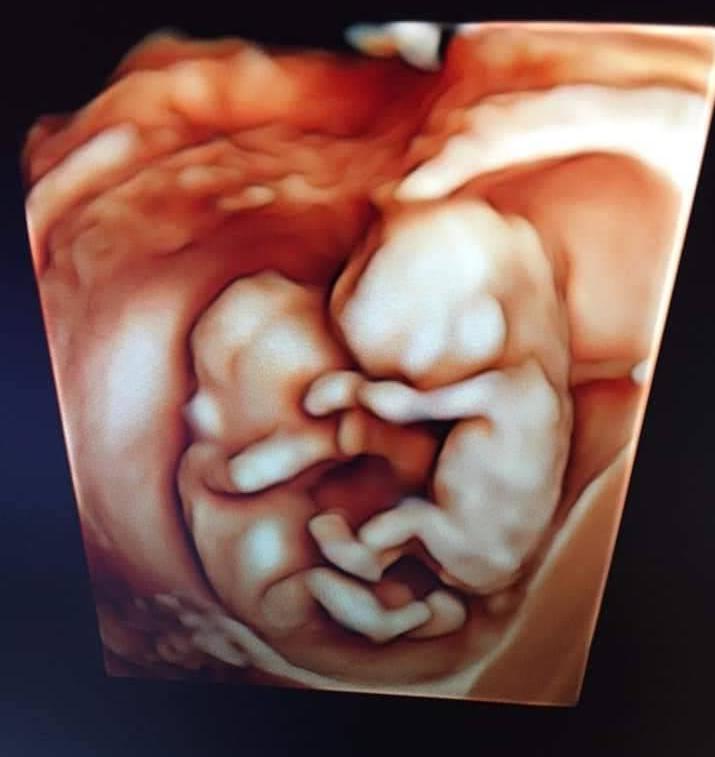

Đây la 1nang 1 chàng trâu của nhà mình đây ạ, 22w 450g va 500g

Cảm ơn Mamibabi rất nhìu á, mẹ thai giáo là 2 con trâu con ngí ngoáy luôn ạ